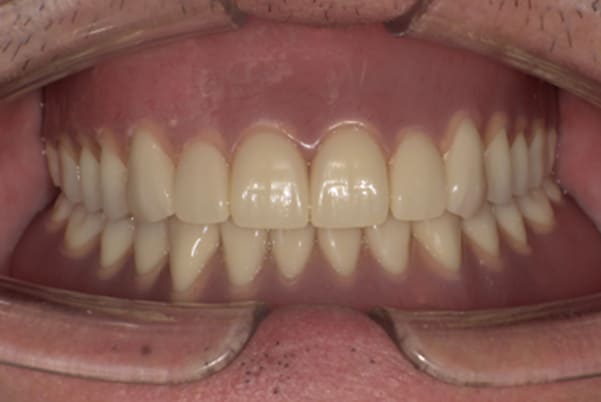

症例レポート[CASE.02]

入れ歯がカパカパして痛い、

歯がぐらぐらする

- 男性(60代)

- 入れ歯がカパカパする、歯がぐらぐらして痛い、食いしばれない

- 上顎精密総金属床総入れ歯

- 下顎精密金属床部分入れ歯

- ジルコニアクラウン4歯

- 上顎精密総金属床総入れ歯:55万円

- 下顎精密金属床部分入れ歯:55万円

(ミリング、ラベット加工込み) - ジルコニアクラウン:11万円×4歯

合計:154万円(税込)

上の前歯が重度歯周病により動揺し、残せない状態のため、入れ歯も動揺がありました。

ご自身の歯に負担の少ないバネ、また見た目も改善

バネをかける歯は繋げることで強度を増し、歯への負担を軽減し、歯の寿命を長くする設計へ。

バネがかかる歯の被せ物は、歯への負担を減らし、入れ歯が動きにくいようになる形態をあらかじめ付与することで、より入れ歯の機能が高まります。

治療を行う際、被せ物や入れ歯は、別々に考えるのではなく、一口腔単位としてお口全体のことを考え最良の治療計画を立てることが歯の寿命、機能効果を向上させるため、専門医としてこのことは常に心掛けて治療を行っています。

残りの歯に負担がかからないよう、被せ物と入れ歯の一体化を図った入れ歯

治療前は上下奥歯の入れ歯が削れていることで、かみ合わせが低くなり唇もつむった状態でした。

かみ合わせを適切な高さに戻したことで、本来の自然な口元へ。